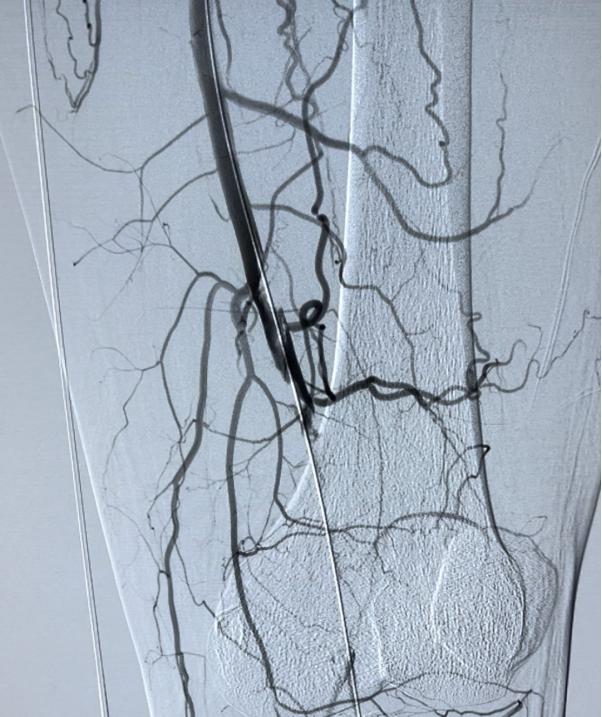

▲治疗前造影,腘动脉完全闭塞

▲抽吸血栓及溶栓后:①腘动脉显影良好;②胫前动脉、胫后动脉、腓动脉显影良好;③足背动脉及足底动脉弓建立。手术非常顺利,格桑先生下肢血管成功开通,避免了被截肢的命运。医院各级领导殷切关心藏族同胞在渝的治疗和生活情况,术后多次看望格桑先生,送上慰问品和祝福。